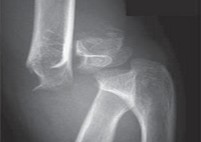

Understanding Upper Limb Trauma: Upper limb trauma refers to injuries that affect the bones, joints, muscles, and soft tissues of the arms, shoulders, elbows, wrists, and hands. These injuries can range from minor fractures to more complex conditions requiring surgical intervention. Common causes of upper limb trauma in children include falls, sports-related accidents, and other forms of trauma.

Accurate Diagnosis: Dr. Desai employs advanced diagnostic techniques to

accurately assess the extent of the injury. This often includes X-rays, MRI scans, and clinical examinations to understand the injury’s impact on growth plates and overall bone health.